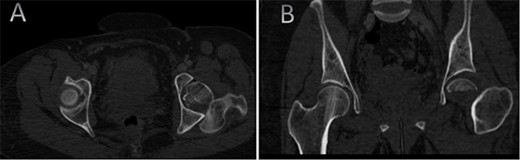

A medically free 42-year female presented to our institute as a life-saving case from a different hospital as she was a victim of unrestrained road traffic accident 2 days prior to presentation. Upon assessment in the emergency department (ER), she was conscious and oriented, and was found to have bilateral lung contusion, and multiple fractures of ribs. She also had a left sided vertical femoral head fracture dislocation comprising around 40% of the femoral head (Fig. 1). Closed reduction under conscious sedation was done in the ER, which was successful based on post-reduction imaging studies (Fig. 2). Her chest injuries were treated with chest tube and observation for 10 days. During that time, discussion was made with the patient regarding her situation and conservative management was chosen by way of bed rest and continuation of skeletal traction for 4 weeks with serial radiographs in the hospital on a weekly basis after clearance of her chest injuries. Skeletal traction was discontinued and she was advised to continue bed to wheelchair mobilization for an additional 2 weeks. After 6-weeks from the injury, a Computed Tomography (CT) was done to the patient and revealed signs of fracture healing (Fig. 3). At 3-years after the injury, she was found to have full painless range of motion of the affected hip and has resumed her activity of daily living without any complaints and the images showed a symmetrical joint space of the hips (Fig. 4).

CT scan of the pelvis showing axial (A) and coronal (B) cuts at 6-week post-injury showing signs of healing of the left fractured femoral head with a concentric hip joint.